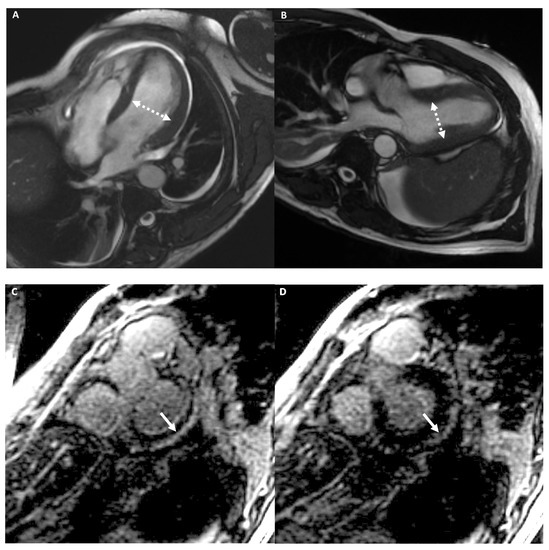

4.2.3. Cardiac Imaging: AH vs. Left Ventricular Non-Compaction

- Negri, F.; De Luca, A.; Fabris, E.; Korcova, R.; Cernetti, C.; Grigoratos, C.; Aquaro, G.D.; Nucifora, G.; Camici, P.G.; Sinagra, G. Left ventricular noncompaction, morphological, and clinical features for an integrated diagnosis. Heart Fail. Rev. 2019, 24, 315–323. [Google Scholar] [CrossRef] [PubMed]

- Stämpfli, S.F.; Donati, T.G.; Hellermann, J.; Anwer, S.; Erhart, L.; Gruner, C.; Kaufmann, B.A.; Gencer, B.; Haager, P.K.; Müller, H.; et al. Right ventricle and outcome in left ventricular non-compaction cardiomyopathy. J. Cardiol. 2020, 75, 20–26. [Google Scholar] [CrossRef]

| Trabeculation | Increased | Increased | Increased | NC/C > 2.3 in two cardiac segments | - | - | - |